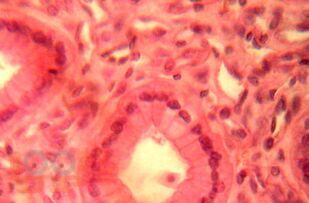

Учебник представляет собой изложение на современном уровне теоретических основ гистологии как науки. В нем освещены общие закономерности строения, функций, развития, регенераторных свойств клеток и тканей, а также эмбрионального развития человека.

Учебник включает такие разделы гистологии, как гистологическая и микроскопическая техника, цитология, эмбриология человека, общая гистология, а также цветной атлас светомикроскопического строения клеток и тканей, эмбриогенеза человека. Большое внимание уделено истории развития гистологии как науки. Материалы этих разделов представлены в 11 главах и имеют выраженную медицинскую направленность. Пособие написано в соответствии с действующей программой по гистологии, цитологии и эмбриологии и предназначается для студентов 1-2 курсов лечебного и стоматологического факультетов высших медицинских учебных заведений, а также может быть полезно аспирантам и молодым преподавателям ВУЗов.